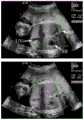

图1~图3为产前超声视频图像示意图;Figures 1 to 3 are schematic diagrams of prenatal ultrasound video images;

如图1~图3所示,为产前超声视频图像示意图,分别是:图1表示腹围切面,含有胃泡(SB),脐静脉(UV)和脊柱(SP);图2表示双眼球横切面,包含鼻骨,眼球和晶状体;图3表示心脏四腔切面,包含左心房(LA),右心房(RA),左心室(LV),右心室(RV)和降主动脉(DAO),其中第一行是标准切面图像,第二行是对应于不同区域的非标准切面图像,对于非专业人士而言,很难看到它们之间的明显差异。在标准切面定义中,要求画面中必须清楚地看到一些关键结构。例如,在双眼球横切面中,必须清楚地看到鼻骨,双侧眼球以及两侧的晶状体,像晶状体这样细微的结构,在图像中可能只占据几个像素,很难被算法识别出来,但它对于出生缺陷诊断来说又非常重要。As shown in Figures 1 to 3, they are schematic diagrams of prenatal ultrasound video images, respectively: Figure 1 shows the section of the abdominal circumference, including the gastric bubble (SB), umbilical vein (UV) and spine (SP); Figure 2 shows the eyes Transverse section, including nasal bone, eyeball and lens; Figure 3 shows the four-chamber section of the heart, including left atrium (LA), right atrium (RA), left ventricle (LV), right ventricle (RV) and descending aorta (DAO), The first row is a standard section image, and the second row is a non-standard section image corresponding to different regions. For non-professionals, it is difficult to see the obvious difference between them. In the standard aspect definition, it is required that some key structures must be clearly visible in the picture. For example, in the cross-section of both eyeballs, the nasal bone, bilateral eyeballs, and lenses on both sides must be clearly seen. Such subtle structures as the lens may only occupy a few pixels in the image, and it is difficult to be recognized by the algorithm. It is also very important for the diagnosis of birth defects.